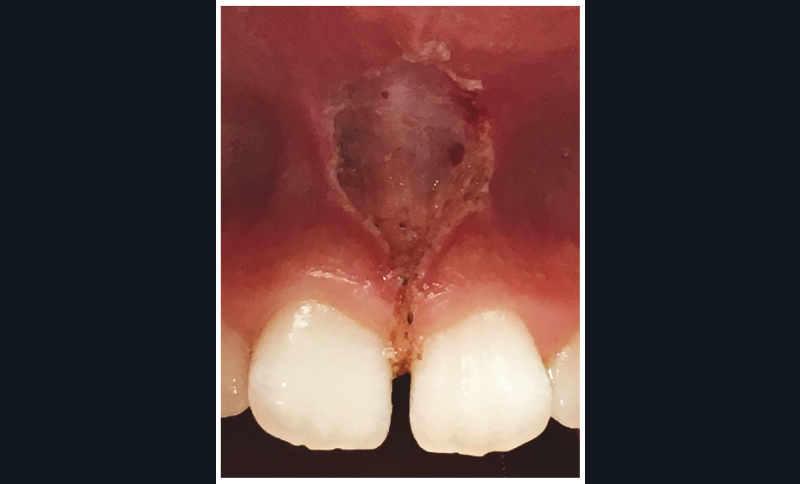

Le laser diode peut être utilisé en microchirurgie pour sectionner les tissus sans effet de carbonisation : il est idéal dans les cas de frénectomie, qui ne nécessiteront donc plus de points de sutures (fig. 2a-c). L’apparition, très tôt, de la fibrine favorise une cicatrisation rapide et sans douleur. Cet effet ablatif sera également appréciable pour la gingivectomie, l’ouverture du sulcus, l’hémostase, l’ablation de mucocèles, de diapneusies, ou encore pour traiter des hémangiomes.